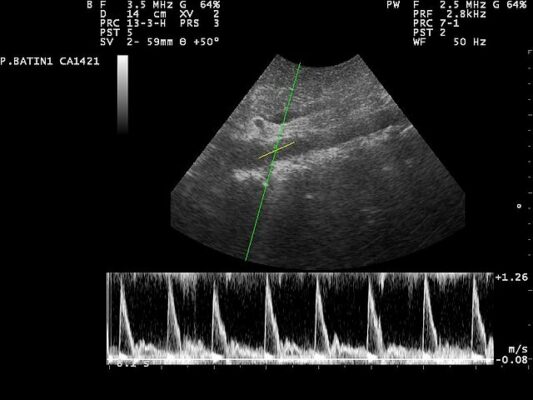

- aort ultrasonu

Aort hastalıklarından şüphelendiğimizde, hastanın anlattıkları ve muayene bulguları çok önemlidir. Ancak kesin tanı koymak ve yol haritamızı çizmek için kullandığımız modern görüntüleme yöntemleri şunlardır:

- Ultrasonografi (USG) ve Ekokardiyografi (EKO)

Ultrason, özellikle karın anevrizmalarının taranması ve takibinde kullandığımız zararsız ve pratik bir yöntemdir. Ekokardiyografi (EKO), yani kalp ultrasonu, aortun kalpten çıkan ilk kısmını değerlendirmede bize hızlıca bilgi verir. Özellikle yemek borusundan yapılan EKO (TEE), göğüs aortasını çok net gösterir.

Ancak acil durumlarda ve cerrahi planlamada altın standart yöntemimiz Bilgisayarlı Tomografi Anjiyografi’dir (BTA). Damardan özel bir ilaç (kontrast madde) verilerek çekilen bu test, aortun tamamını üç boyutlu olarak haritalandırır. Bize yırtığın tam yerini, anevrizmanın boyutunu, organlara giden dalların durumunu ve tedavi için gerekli olan tüm kritik bilgileri saniyeler içinde sunar. Manyetik Rezonans (MRA) ise radyasyon içermediği için özellikle genç hastalarda veya düzenli takip gereken durumlarda tercih ettiğimiz değerli bir alternatiftir.